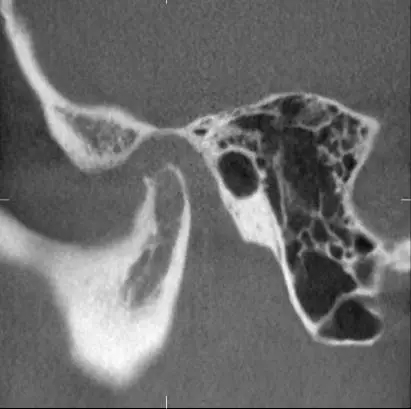

第二,完全埋在骨頭里可以不拔?

完全埋在牙槽骨里的下頜智齒,它本身倒是不出問(wèn)題。但是這些近中或水平阻生的智齒,會(huì)推擠下頜第二磨牙,導(dǎo)致第二磨牙伸長(zhǎng):

然后,第二磨牙造成咬合干擾、早接觸,前牙開(kāi) 牙合…………

甚至髁突吸收:

所以,這種智齒也還是要 拔掉。